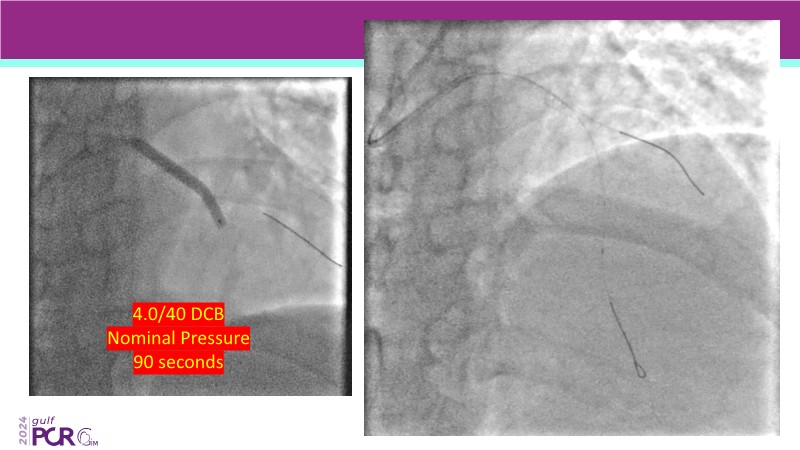

Explore cutting-edge strategies for optimizing drug-coated balloon (DCB) procedures in this session. Uncover practical tips to improve outcomes, review key indications, and examine international consensus on DCB use. Case presentations and expert discussions offer insights to refine your approach.

- To learn the tips and tricks to improve the result with drug coated balloon strategy